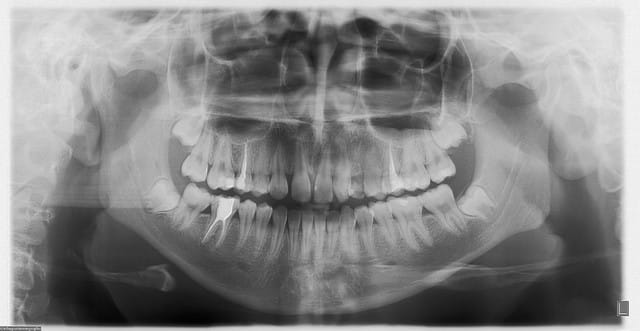

allez...suite des gammes...entre deux "regards" sur doctissimo...(on se marre bien...Sid est déchaîné...)

bon , patiente 60ans...pas de pbs médicaux...paro...moyenne mais pas trop mal stabilisée...y a mieux...c'est sûr...(j'entends déjà les "foudres" de Noah...)

os type 3...pas top...d'où compression/expansion...

3 implants posés en 36, 37, et 15...

les implant en 15 et 36 sont des 4.7mm par 11.5mm et l'implant en 37 est un 3.7mm par 10mm (pas assez de place au niveau proth pour 2 4.7mm...)

juste un ptit problème de dernière minute pour l'implant en 37...l'expansion finale de l'implant mis en 36 a un peu fissuré la crête...me faisant perdre un peu de stab primaire...rien de dramatique...mais j'ai préféré du coup enfouir...

j'avais oublié...la pano...

pour les photos, c'est mieux...pas encore Yann Arthus Bertrand...mais là çà peut aller...on progresse, on progresse...